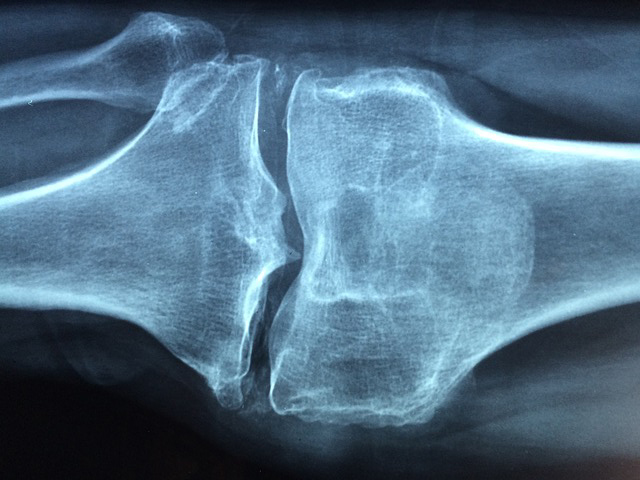

港大利用公立醫院臨床資料庫,從2010至2014年確診的心房顫動患者中,找出8,152名獲處方傳統藥華法林及新藥達比加群的新症患者進行觀察。500天後,發現約4,900名服用華法林患者中,有104人有骨質疏鬆性骨折;3,270名服用達比加群患者中,則有32人出現骨質疏鬆性骨折。研究發現,服用達比加群的患者,其骨質疏鬆性骨折的風險是每年0.7%,即每1,000人當中每年有7人骨折,相對風險比服用華法林的0.11%低36%。